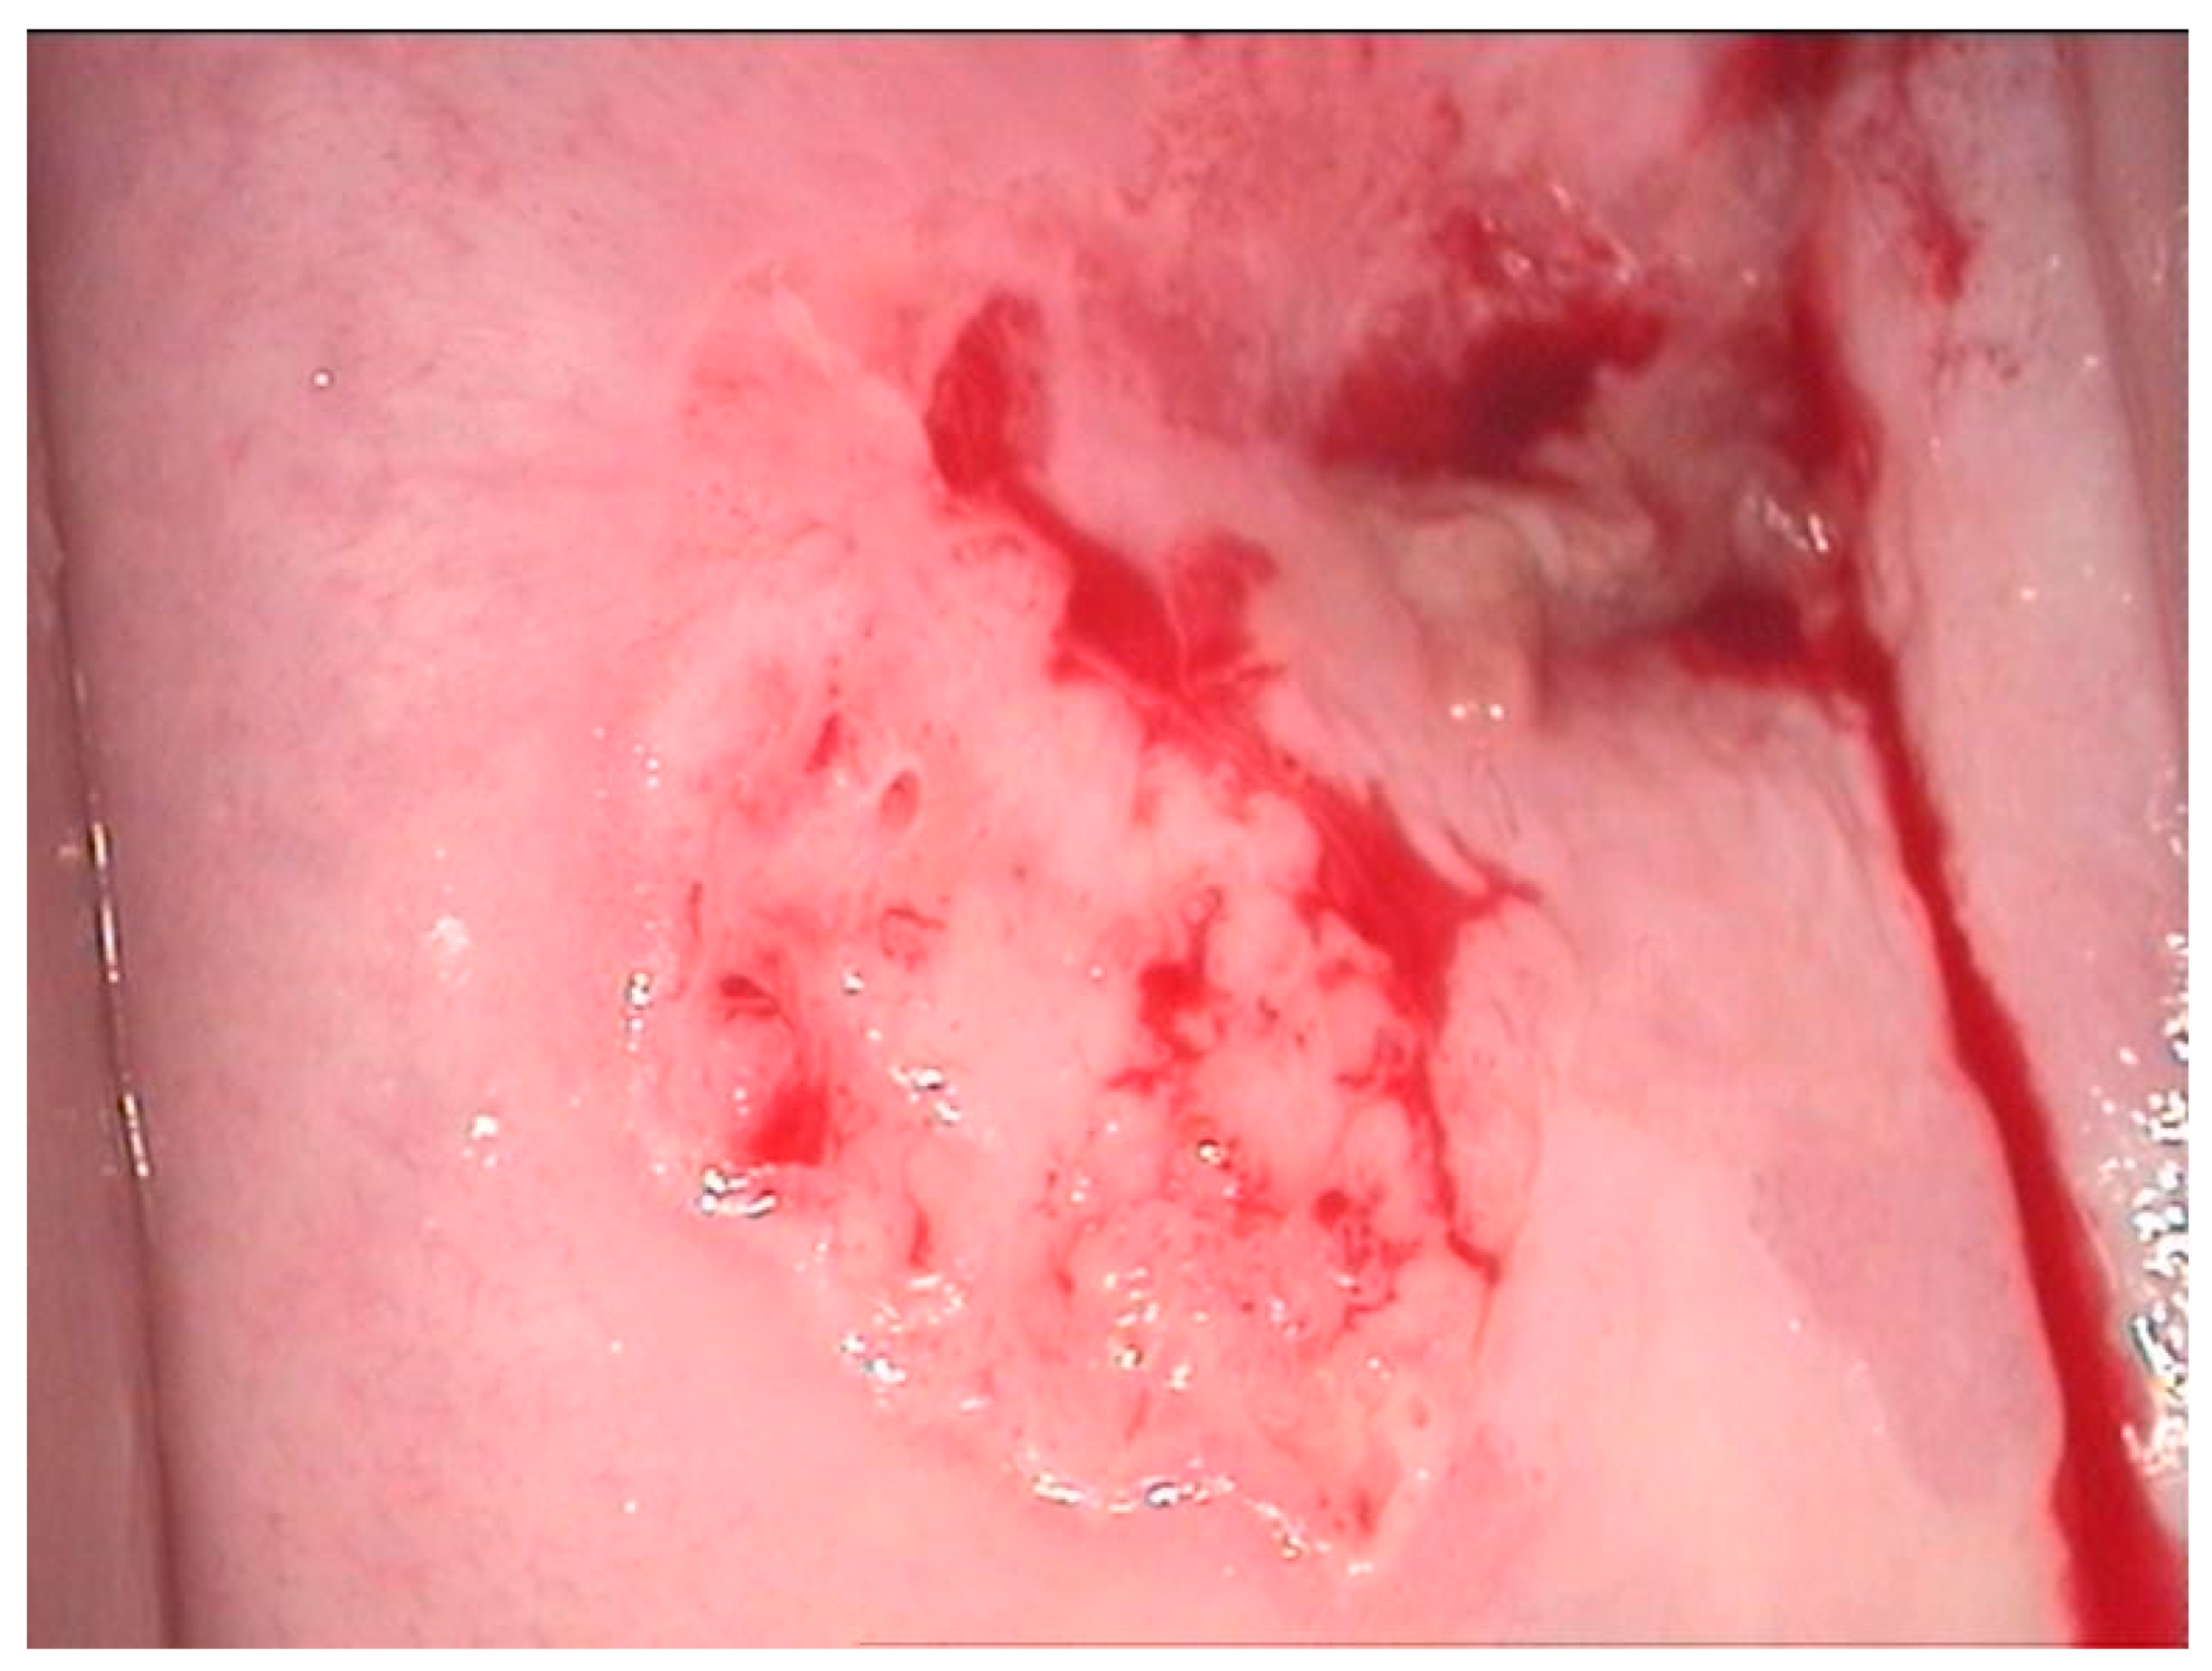

2.2. Clinical Examination